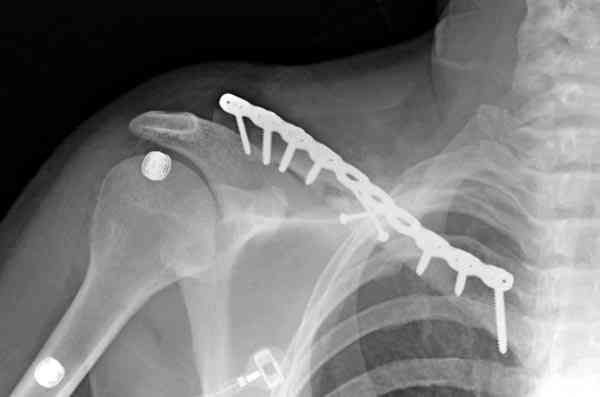

Консервативное лечение, через 8 мес. операция Rockwood pin с костной пластикой в нашем городе другим врачом. После 8 недели падение, гвоздь удален оперирующим хирургом, больная направлена к нам. Фиксация реконструктивной пластиной с трикортикальным графтом, добавлен BMP-2. Для стабилизации фиксацию провели через акромион.

Вот уже два месяца больная также продолжает жаловаться на боли, буквально на днях удалили акромиальную часть пластины с специальной пилой с алмазным покрытием для медицинского металла. До сих пор судьба ложного сустава неизвестна....